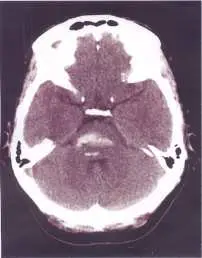

44 歲女性有酗酒習慣,某日熬夜喝酒之後突然口語不清,吞嚥困難,因此被送到急診求治;患者未注射對比劑的電腦斷層掃描檢查如圖,最可能的診斷為何?

本題考查後顱窩(posterior fossa)出血性病變的電腦斷層(CT)影像判讀,以及酗酒相關腦幹出血(brainstem hemorrhage)的臨床特徵。重點在於區分腦幹出血與小腦出血的 CT 影像位置與臨床表現。

非對比劑 CT(non-contrast CT)影像所見:

- 高密度病灶(hyperdense lesion):影像中後顱窩可見一明顯白色高密度區域,代表急性出血(血液在 CT 中呈高密度,Hounsfield unit 約 50–80 HU)

- 病灶位置:高密度病灶位於後顱窩的中央/旁中央區域,對應解剖位置為腦幹(brainstem),尤其是橋腦(pons)部位,而非小腦半球(cerebellar hemisphere)外側

- 小腦半球外觀:雙側小腦半球密度相對正常,未見明顯局部高密度病灶

- 第四腦室:第四腦室受壓,可能有輕度受壓或移位

- 結論:影像表現與**腦幹出血(brainstem hemorrhage)**最為一致,具體為橋腦出血(pontine hemorrhage)